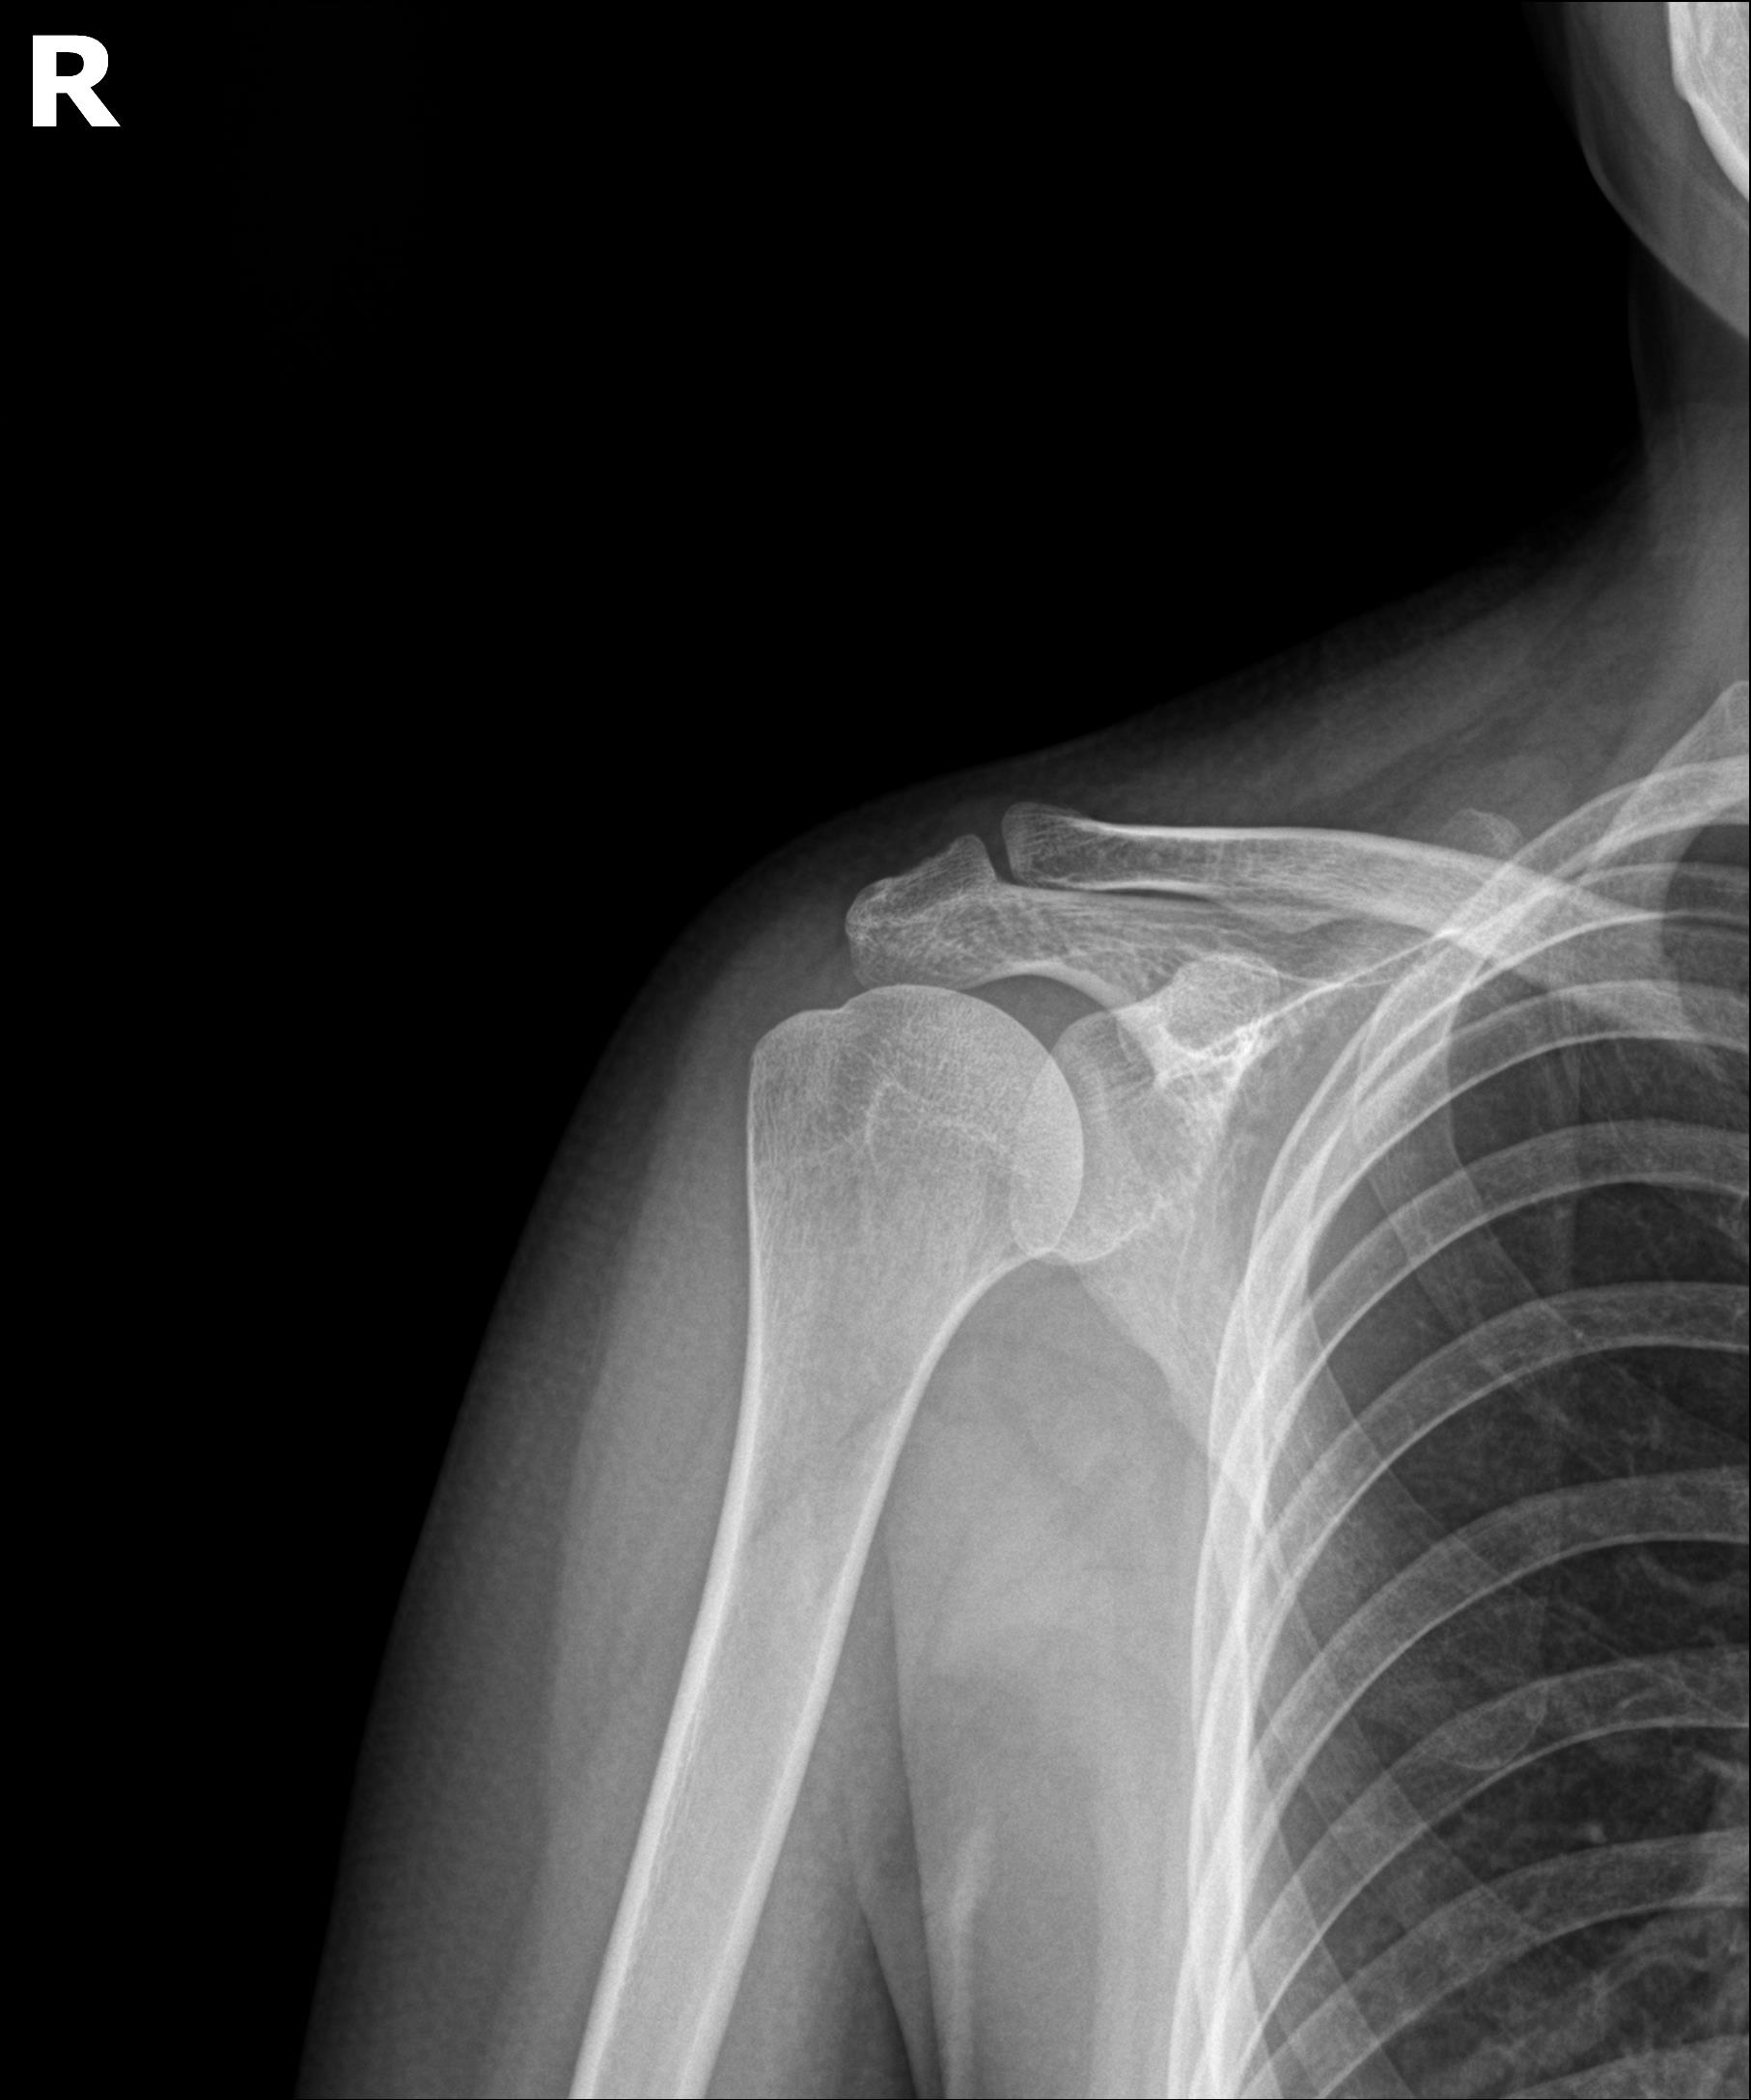

40대 초반의 여성 환자분이 내원하셨습니다. 1년 전부터 오른쪽 어깨에 극심한 통증이 있었고, 밤에는 잠을 잘 수 없을 정도였다고 합니다.

처음에 동네 정형외과에서 X-ray 찍으니까 석회가 있대요. 충격파 치료 받았는데 안 낫고, 그래서 석회 빼는 주사 시술 받으러 다른 병원 갔어요.

환자분은 3개월에 걸쳐 3회의 '석회흡입술'을 받으셨습니다.

그때마다 '조금씩 빠지고 있다'고 했는데... 시술받고 나면 오히려 더 아프고, 통증은 그대로고. 결국 다시 X-ray 찍어보니까 석회가 거의 그대로 있대요. 의사 선생님이 '석회가 너무 단단해서 주사로는 안 빠진다, 관절경 수술해야 한다'고...

환자분의 눈에는 지침과 두려움이 묻어 있었습니다.

선생님, 정말 수술밖에 방법이 없는 건가요?